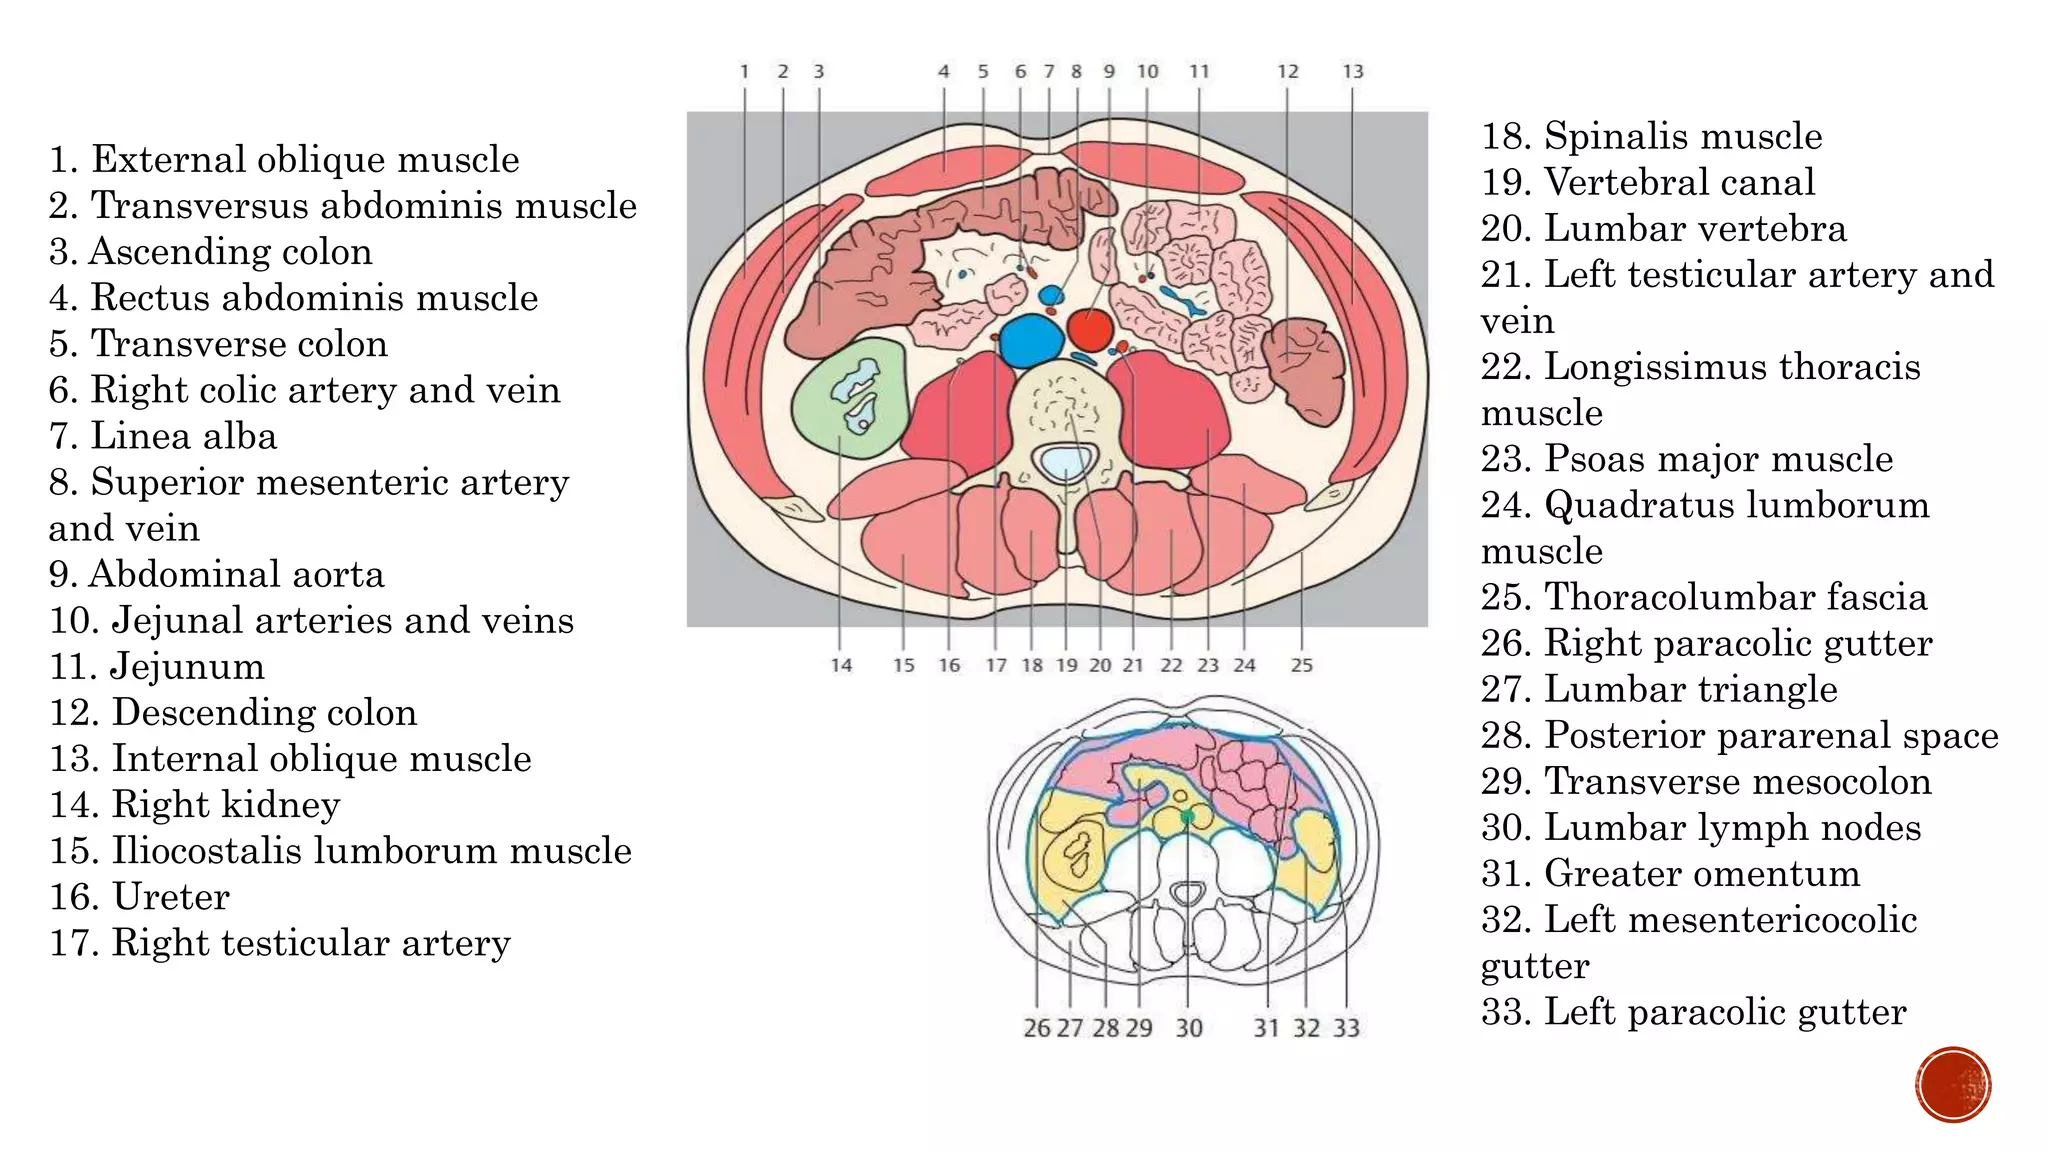

The document describes the anatomy of the abdomen and pelvis region of the human body. It lists over 40 structures and their locations, including major organs like the liver, kidneys, intestines, blood vessels and muscles of the abdominal wall and pelvis. The structures are grouped into sections focusing on different anatomical areas like the abdomen, retroperitoneum, pelvis and gluteal region.